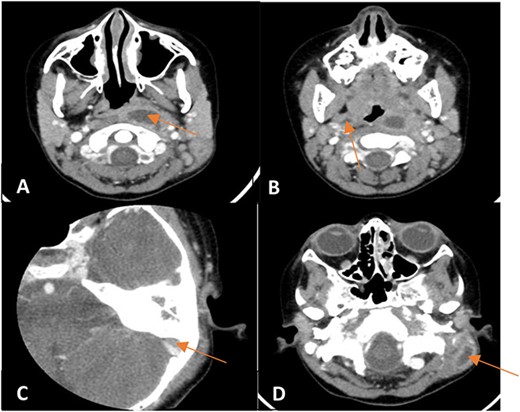

A contrasted CT scan (Fig. 2) confirmed the presence of a left parapharyngeal abscess (2.7 × 1.2 × 3.7 cm) with a smaller right abscess (0.8 × 0.5 × 1.3 cm). Also, a left subdural abscess (1.1 × 0.4 cm) and a postauricular irregular collection at the proximal SCM measuring 1.9 × 0.9 × 2.8 cm were noted.

Enhanced CT scan of the temporal bones and neck showing (A) a left parapharyngeal space fluid collection with enhancing walls, (B) a small right parapharyngeal collection with minimally enhancing walls, (C) an intracranial extension of mildly enhancing lesion to subdural space and (D) a left mastoid bone showing lateral wall cortical disruption with adjacent retro-auricular irregular collection with enhancing walls.